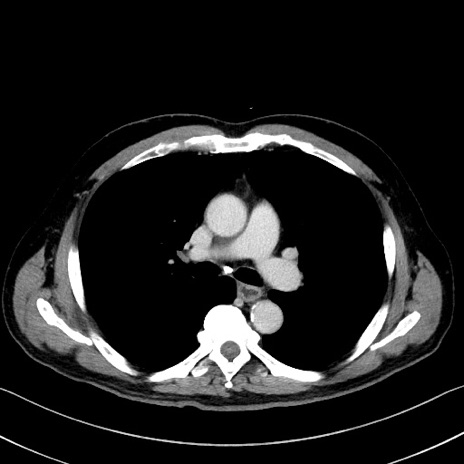

症例35(横断像)

【症例】70歳代 男性

【主訴】腹部膨満、嘔吐

【現病歴】昨日より腹部膨満感出現。本日増悪し、仙痛出現。嘔吐あり、受診。

【既往歴】糖尿病、胆摘後

【身体所見】BP 149/80mmHg、HR 74/min、BT 35.9℃、腹部:膨満、軟、圧痛なし。腸雑音減弱あり。上腹部正中切開瘢痕あり。

【データ】WBC 13500、CRP 1.72